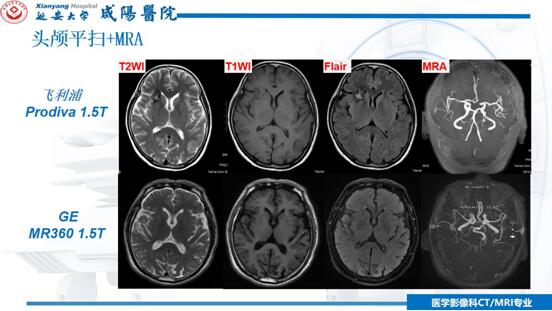

本次會議劉連鋒主任分別對飛利浦Prodiva與GE-MR360兩臺1.5T磁共振設備的掃描方式、圖像質量及臨床應用進行客觀的分析與詳細的對比,對顱腦、眼眶、垂體、神經、脊柱、四肢關節、腹部及盆腔等部位常用的掃描序列進行細致講解與對照,對呈現的圖像質量進行分析及對比,對兩臺設備如何更好的應用臨床并開展符合科室特點的實用性技術進行指出和說明,使與會人員深受啟發并清晰明確工作方向。

劉連鋒主任指出,飛利浦Prodiva1.5T與GE-MR360兩臺1.5T磁共振設備磁共振在功能成像,如類PET、3D-ASL、DTI、高清DWI、4D-MRA,尤其是高分辨血管壁成像和CE-MRA等檢查項目上,擁有圖像清晰度高、檢查時間快等優勢,我們要發揚這種優勢,更好的為患者提供優質的服務,同時要加深與臨床科室的合作,開展實用性技術。我們相信,在新設備、新技術項目的臨床應用實踐中,在總結經驗、對比學習的過程中,在提高自身業務能力、不斷探索的努力下,我院CT/MRI室將更好的與臨床合作、服務于廣大患者,為精準診斷、精準治療、真誠服務、健康同行這一目標不斷努力,不斷前行!